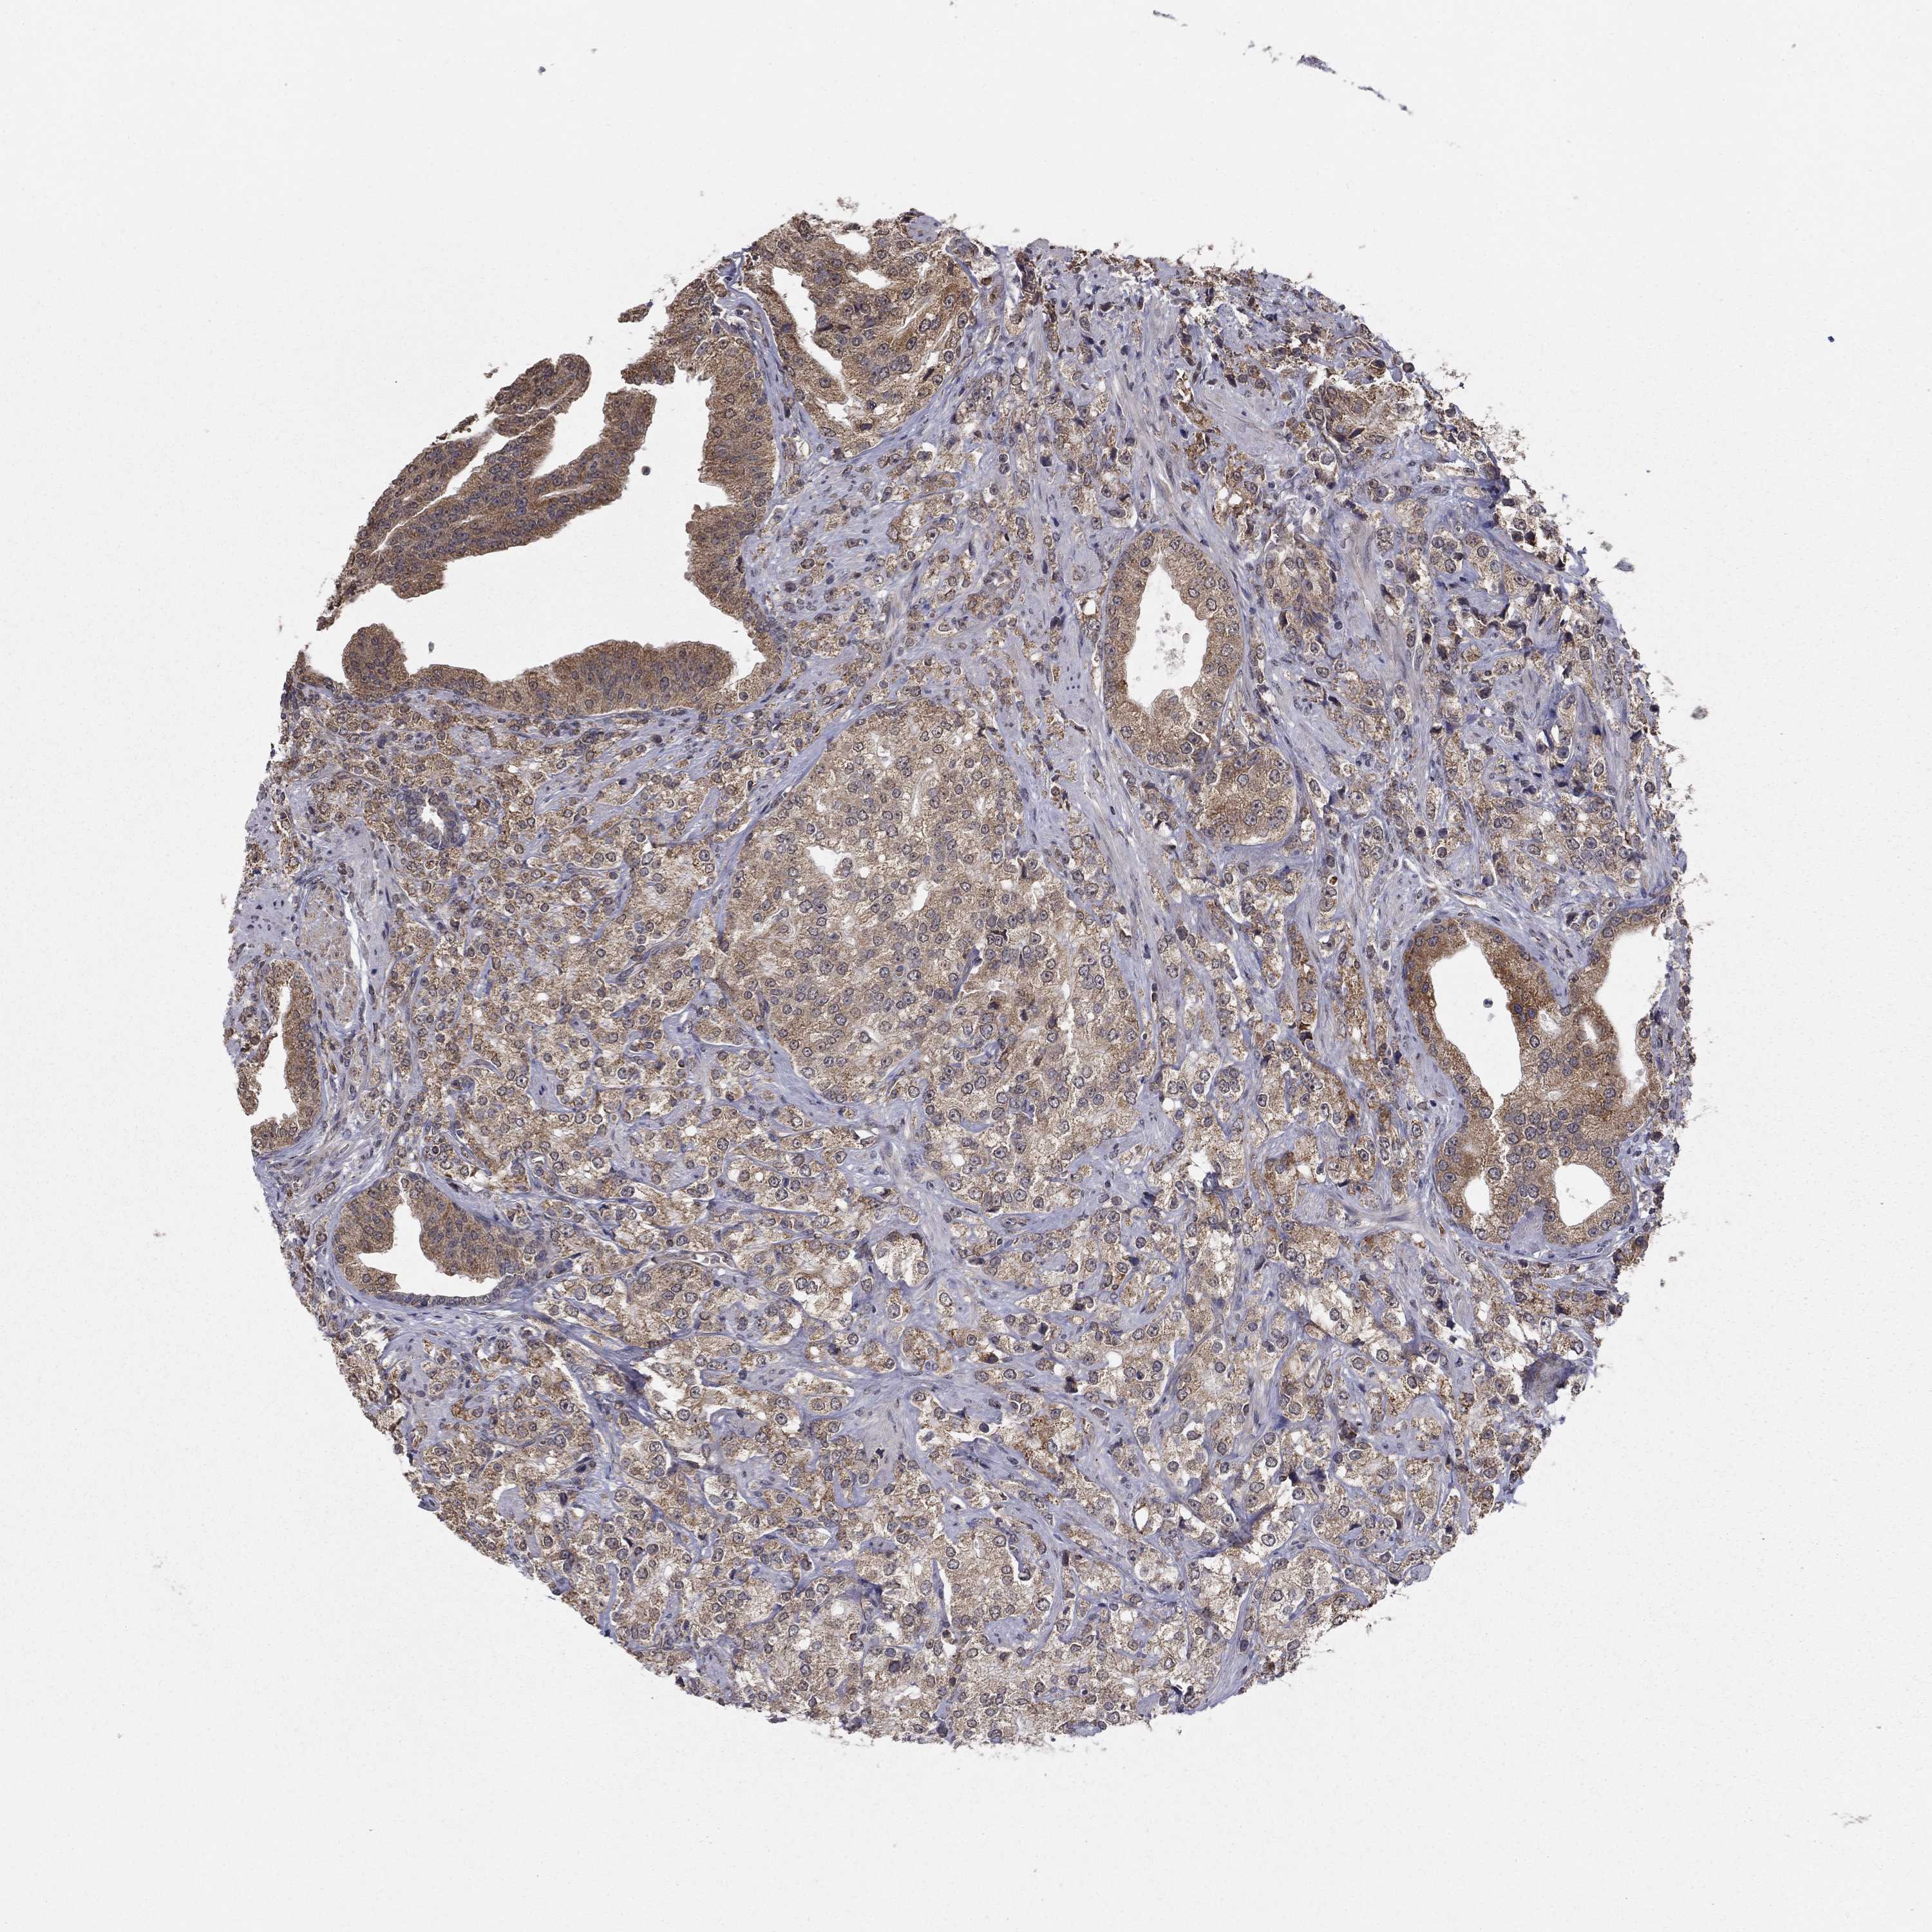

PROSTATE CANCER - Protein expressioni

A mouse-over function shows sample information and annotation data. Click on an image to view it in a full screen mode. Samples can be filtered based on level of antibody staining by selecting one or several of the following categories: high, medium, low and not detected. The assay and annotation is described here.

Note that samples used for immunohistochemistry by the Human Protein Atlas do not correspond to samples in the TCGA dataset.

Antibody stainingi

Antibody staining in the annotated cell types in the current human tissue is reported as not detected, low, medium, or high, based on conventional immunohistochemistry profiling in selected tissues. This score is based on the combination of the staining intensity and fraction of stained cells.

Each image is clickable and will lead to virtual microscopy that enables deeper exploration of all samples and also displays staining intensity scores, fraction scores and subcellular localization as well as patient and tissue information for each sample.

Antibody HPA006584

Antibody HPA061679

Staining

High

Medium

Low

Not detected

Intensity

Strong

Moderate

Weak

Negative

Quantity

>75%

75%-25%

<25%

None

Location

Nuclear

Cytoplasmic/membranous

Cytoplasmic/membranous,nuclear

Adenocarcinoma, Low grade

Adenocarcinoma, High grade

Adenocarcinoma, NOS